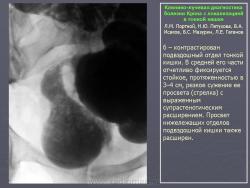

В дифференциально-диагностическом плане интересно -